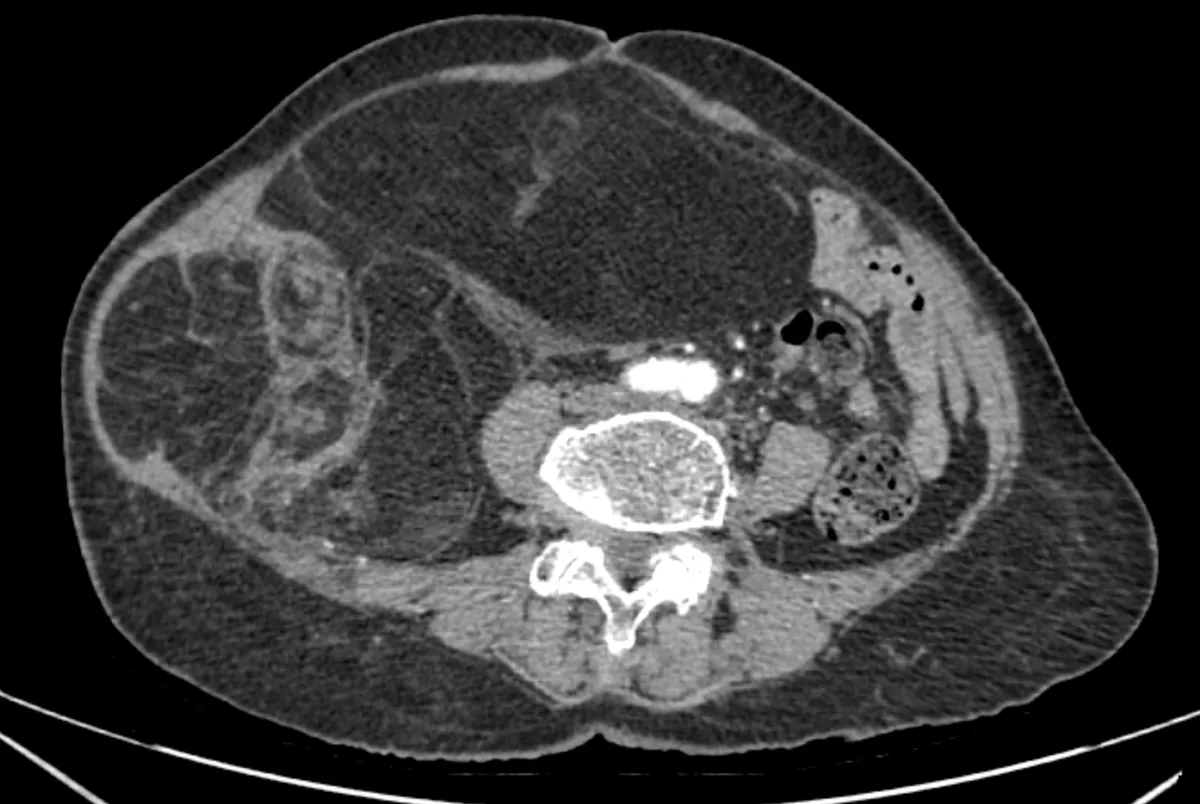

Phim chụp CT ổ bụng

Chẩn đoán hình ảnh (CT ổ bụng có thuốc cản quang) cho thấy khối choán chỗ sau phúc mạc, kích thước 28 × 15 cm, cấu trúc hỗn hợp tổ chức mỡ – đặc , đè đẩy tạng trong ổ bụng nhưng không có dấu hiệu xâm lấn các tạng lân cận. Kết hợp lâm sàng và hình ảnh học, bệnh nhân được chẩn đoán sarcoma mỡ sau phúc mạc.